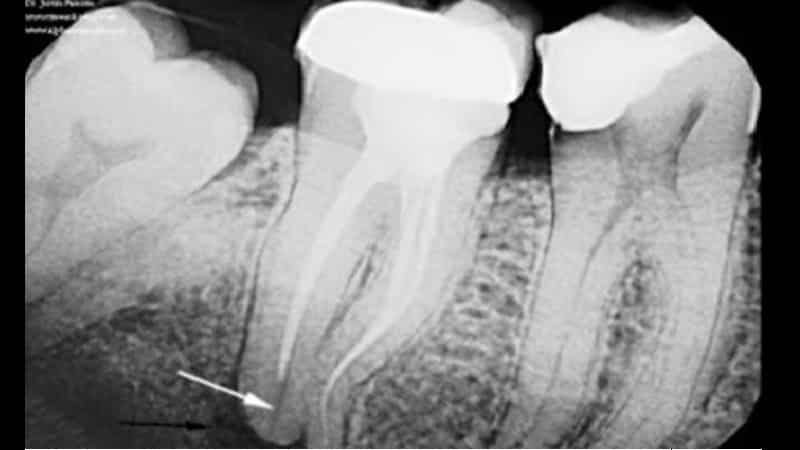

Подготовка к протезированию зубов включает в себя ряд обязательных процедур, которые должен выполнить стоматолог. Корневые каналы обычно заполняются после удаления пульпы, что подразумевает избавление от сосудисто-нервного пучка внутри зуба. Правильно запломбированные каналы помогают избежать воспалительных процессов в области корней зуба. Однако иногда бывает, что корневой канал не заполняется полностью, что может привести к развитию инфекции и образованию гноя. Это состояние называется периодонтитом. Еще одной проблемой, связанной с недостаточной подготовкой, является обтурация пломбировочным материалом, когда пломбирование выполнено до верхушки корня, но не достаточно плотно. В результате образуются пустоты и пористость, что также может вызвать периодонтит. Плохую обтурацию можно выявить на рентгеновском снимке.

Боль в десне под протезами может возникать и в случае перфорации. Перфорация — это искусственное отверстие в стенке зуба, которое появляется из-за некачественной обработки инструментом. Ошибка может быть допущена стоматологом при неправильном расширении корневого канала. Также перфорация может произойти из-за несоблюдения правил фиксации штифта в корневом канале. Рентгенография и клинические симптомы помогают выявить такие ошибки.

Киста может проявляться периодической припухлостью десны в месте больного зуба, но иногда не дает никаких признаков или со временем увеличивается. Определить наличие кисты можно с помощью рентгеновского снимка.